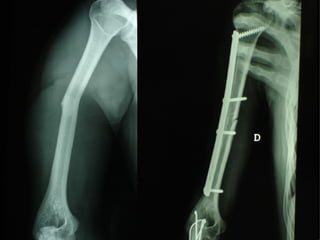

Dal Gennaio 2000 al Febbraio 2006 abbiamo trattato 167 fratture chiuse  con placca percutanea  in 164 pazienti :  27 lesioni diafisarie di gamba, 12 piloni tibiali ,  11 fratture prossimali di tibia, 36 fratture sovracondiloidee di femore, 17 fratture diafisarie di femore, 43 fratture metaepifisarie prossimali di omero, 21 diafisarie d’omero.  156 guarigioni 8 fallimenti

I buoni risultati ottenuti dipendono da 5 punti fondamentali:   una accurata riduzione percutanea della frattura  precise vie di accesso  l’utilizzo della placca che consenta il più lungo braccio di leva possibile il pretensionamento della placca  una sintesi con un ridotto numero di viti

Placche lunghe e pretensionate

Placche lunghe e pretensionate Sintesi con un ridotto numero di viti

Fratture  esposte